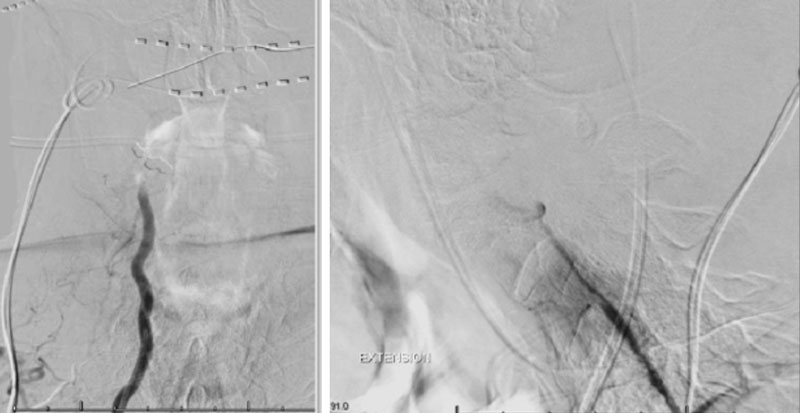

Dynamic provocative fluoroscopy failed to reveal significant Vertebral osseous instability (Figure 2A), however, Transcranial Doppler Flow velocities in the distal right Vertebral and Basilar Artery are markedly reduced during Extension of the Neck (Figure 2B).

On rotation to the left, the patient experienced mild symptoms, however no significant Vertebral Artery or basilar reduction in flow was observed. On rotation to the right, the patient experiences slightly more moderate symptoms, however no significant Vertebral Artery or vascular reduction flow was observed. On hyper extension of approximately 10-15 degrees, passively performed by the patient until symptoms are reproduced, angiogram demonstrates complete occlusion of the right Vertebral Artery at approximately the C2-C1 level. (Figure 5)